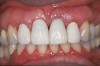

Fig 3. Preoperative image of tooth No. 8.

Figure 3